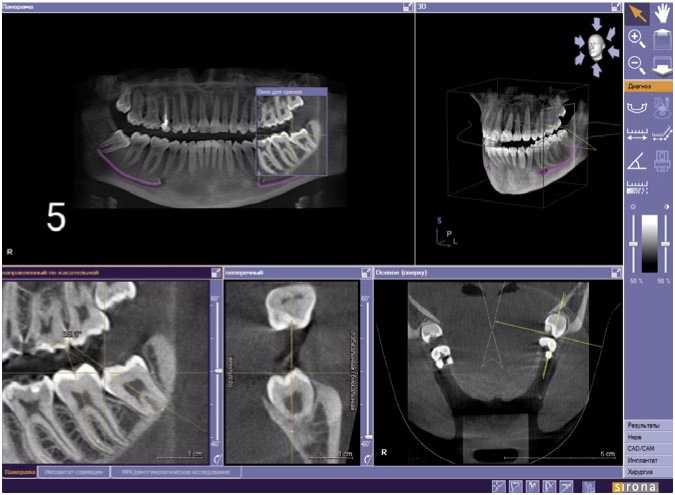

Далее КЛКТ-исследования зубочелюстной системы пациента К. проводили в динамике: КТ-1 в возрасте 16 лет (Рис. 1), КТ-2 – в 18 лет (Рис. 2) и КТ-3 в возрасте 19 лет (Рис. 3) с интервалами 28 и 6 месяцев, соответственно. При сравнении значений КТ-1 и КТ-2 выявлена положительная динамика изменения положения зуба 3.8 (уменьшение угла между зубами 3.7 и 3.8), рост корней в длину. Динамика на КТ-2 и КТ-3 была незначительна, что дает основание считать интервал между КТ-исследованиями менее 6 месяцев малоинформативным. В итоге, по истечению 3 лет наблюдений имеем изменение положения зачатка зуба 3.8 и тенденцию к самостоятельному прорезыванию.

Рис. 2. Пациент К., 18 лет. Срез компьютерной томограммы. Изменение положения зачатка зуба 3.8.